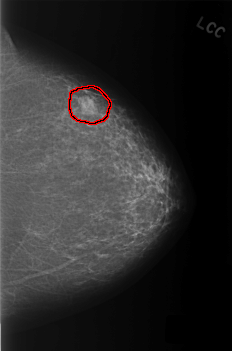

FILE: C_0331_1.LEFT_CC.OVERLAY

TOTAL_ABNORMALITIES 1

ABNORMALITY 1

LESION_TYPE MASS SHAPE LOBULATED MARGINS OBSCURED

ASSESSMENT 3

SUBTLETY 5

PATHOLOGY BENIGN

TOTAL_OUTLINES 1

BOUNDARY